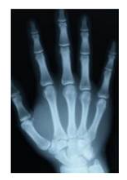

Đây là hình ảnh bàn tay được chụp

Đây là hình ảnh bàn tay được chụp bằng

Nhận biết ứng dụng của các loại tia trong y tế thông qua hình ảnh trực quan.